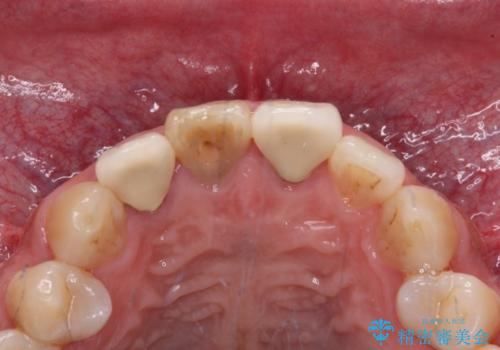

数年前、外傷により両隣の歯とともに根管治療を行い、その後両隣の歯はオールセラミッククラウンにて補綴したそうです。

時間の経過とともに、セラミックにしなかった当該歯の変色が目立つようになり、オールセラミッククラウンにて補綴することとしました。